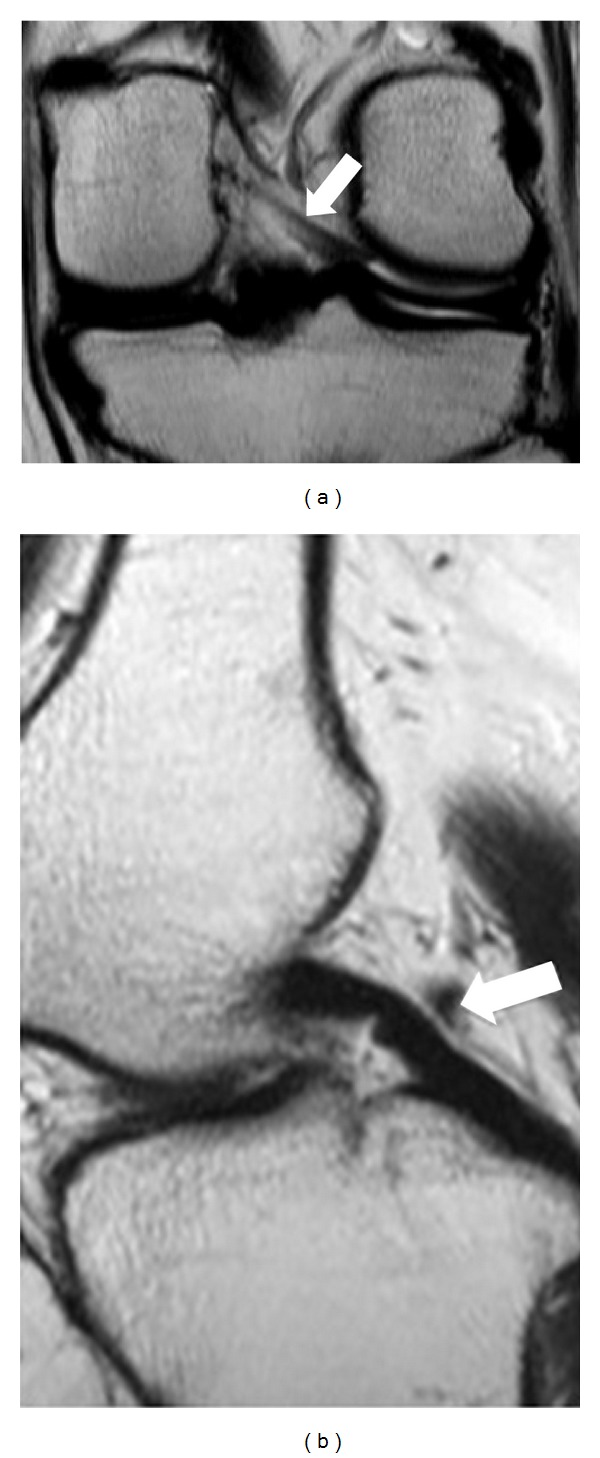

虽然半月板股骨韧带是不同的解剖单位,但从解剖学和放射学的角度来看,其解剖和功能存在争议。回顾性研究了500例膝关节MR检查,以证明其发病率和性别、年龄分布的变化,以及磁共振成像半月板股骨韧带的解剖结构。患者大多是男性,有312人,相比之下,女性患者较少,有188人。纳入这项研究的患者平均年龄为46岁。其中一半以上的人年龄在20到40岁之间;20 ~ 30岁133例,31 ~ 40岁101例,共234例。

Although meniscofemoral ligaments are distinct anatomic units, their anatomy and function are controversial from an anatomic and radiologic point of view. Five hundred knee MR examinations were retrospectively studied in an effort to demonstrate the incidence and variations regarding sex and age distribution, as well as the anatomy of the meniscofemoral ligament at magnetic resonance imaging. Patients were mostly men, three hundred and twelve, in contrast with women who were fewer, one hundred eighty-eight patients. The mean age of the patients who were included in this study was 46 years. More than half of them were between 20 and 40 years old; one hundred thirty-three patients among 20 to 30 years old and one hundred and one patients among 31 and 40 years old, in total two hundred thirty-four patients.